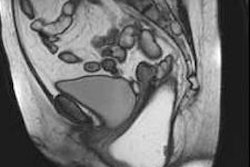

T2 turbo spin-echo imaging (A) of the female pelvis revealing good quality delineation of the zonal anatomy of the uterus. 2D FLASH post-contrast imaging (B) shows lack of enhancement of the ovarian cysts (arrows). The thin arrow in figure B marks a residual inhomogeneity artifact in the right gluteal muscle. All images courtesy of Dr. Lale Umutlu.

T2 turbo spin-echo imaging (A) of the female pelvis revealing good quality delineation of the zonal anatomy of the uterus. 2D FLASH post-contrast imaging (B) shows lack of enhancement of the ovarian cysts (arrows). The thin arrow in figure B marks a residual inhomogeneity artifact in the right gluteal muscle. All images courtesy of Dr. Lale Umutlu.Ultrahigh-field (7-tesla) MR systems have been successfully implemented for in vivo human imaging and are becoming increasingly established for structural and functional brain imaging at research sites worldwide, wrote Dr. Lale Umutlu, from the department of diagnostic and interventional radiology and neuroradiology at University Hospital Essen, and colleagues.

The researchers found 2D FLASH MRI offered the best overall image quality (mean contrast-enhanced 4.9) and highest tissue contrast (mean contrast-enhanced 4.7), while T2-weighted TSE imaging provided moderate to high conspicuity of the uterine zonal anatomy, with mean scores ranging from 3.5 for endometrium to 4.65 for myometrium. Overall image impairment was rated strongest for T2-weighted MRI (2.9) and least for 2D FLASH MRI (mean 4.2).

T1-weighted fat-saturated 2D FLASH MRI resulted in good image quality, providing excellent tissue contrast and high spatial resolution and revealed the potential for ultrahigh-field perfusion MRI, enabling further evaluation of possible pelvic pathologies.

T2-weighted TSE MRI showed high-quality delineation of specific uterine anatomy with comparable contrast to lower field strengths, yet remained challenging because of limitations associated with ultrahigh magnetic field strength, they wrote.